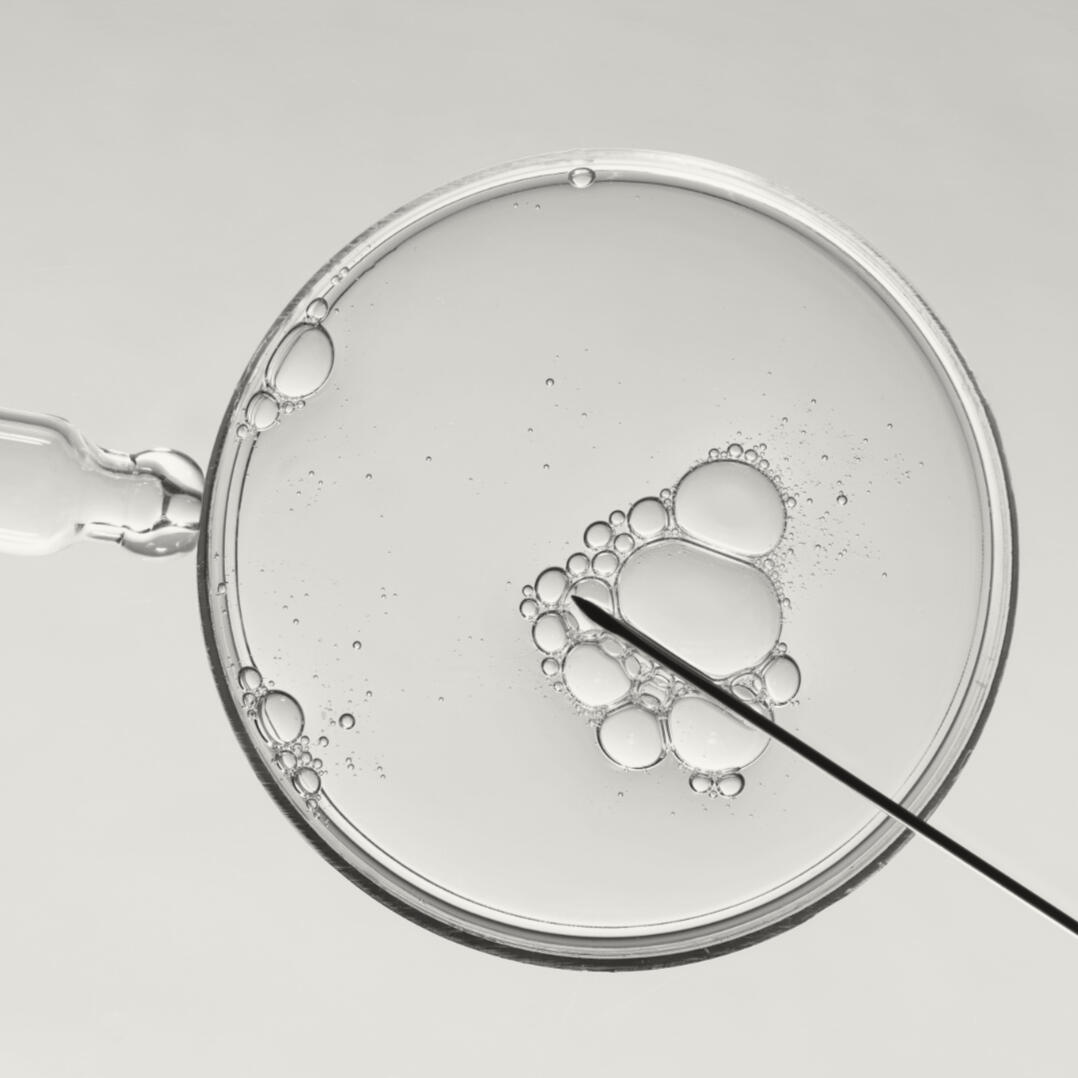

In Vitro Fertilization

IVF

We will fight until we outlaw IVF and all abominable means of medical and scientific research conducted on children.